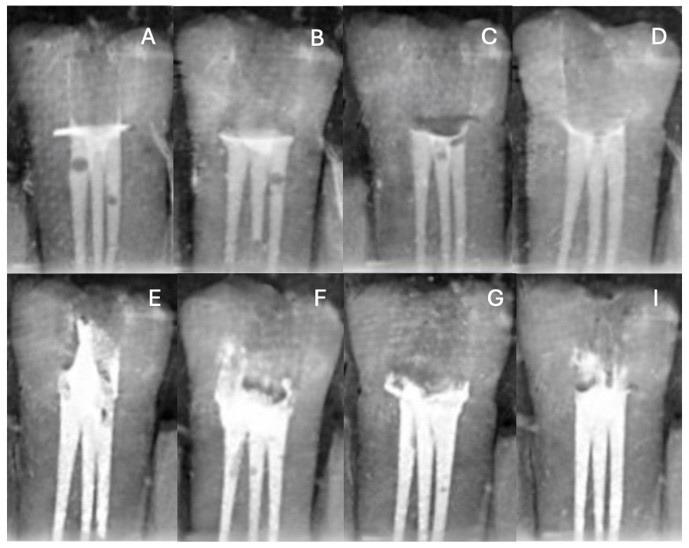

Materials and methods: Primary root canal filling pastes containing calcium hydroxide with barium sulphate and calcium hydroxide with iodoform were heated to four different temperatures (4°C, 23°C, 39°C and 55°C). After instrumentation, 80 endodontic blocks were filled with the heat-treated sealers. Digital radiographs were taken and analysed. The results were analyzed using Tukey's HSD, two-way Robust ANOVA, and the Bonferroni test for multiple comparisons.

Results: The results of this study, the obturation radiopacity values of calcium hydroxide paste containing barium sulphate showed significant differences at different temperature values. Paste at 4°C showed significantly higher radiopacity (p<0.001). Paste at 55°C showed both significantly higher radiopacity (p<0.001), and the total unfilled area values obtained at 55°C was found to be significantly lower than the other temperatures (p=0.025).

Conclusion: It was observed that the preheating process had a positive effect both on the filling quality and hermetic obturation capacity of primary root canal sealants at high temperatures.